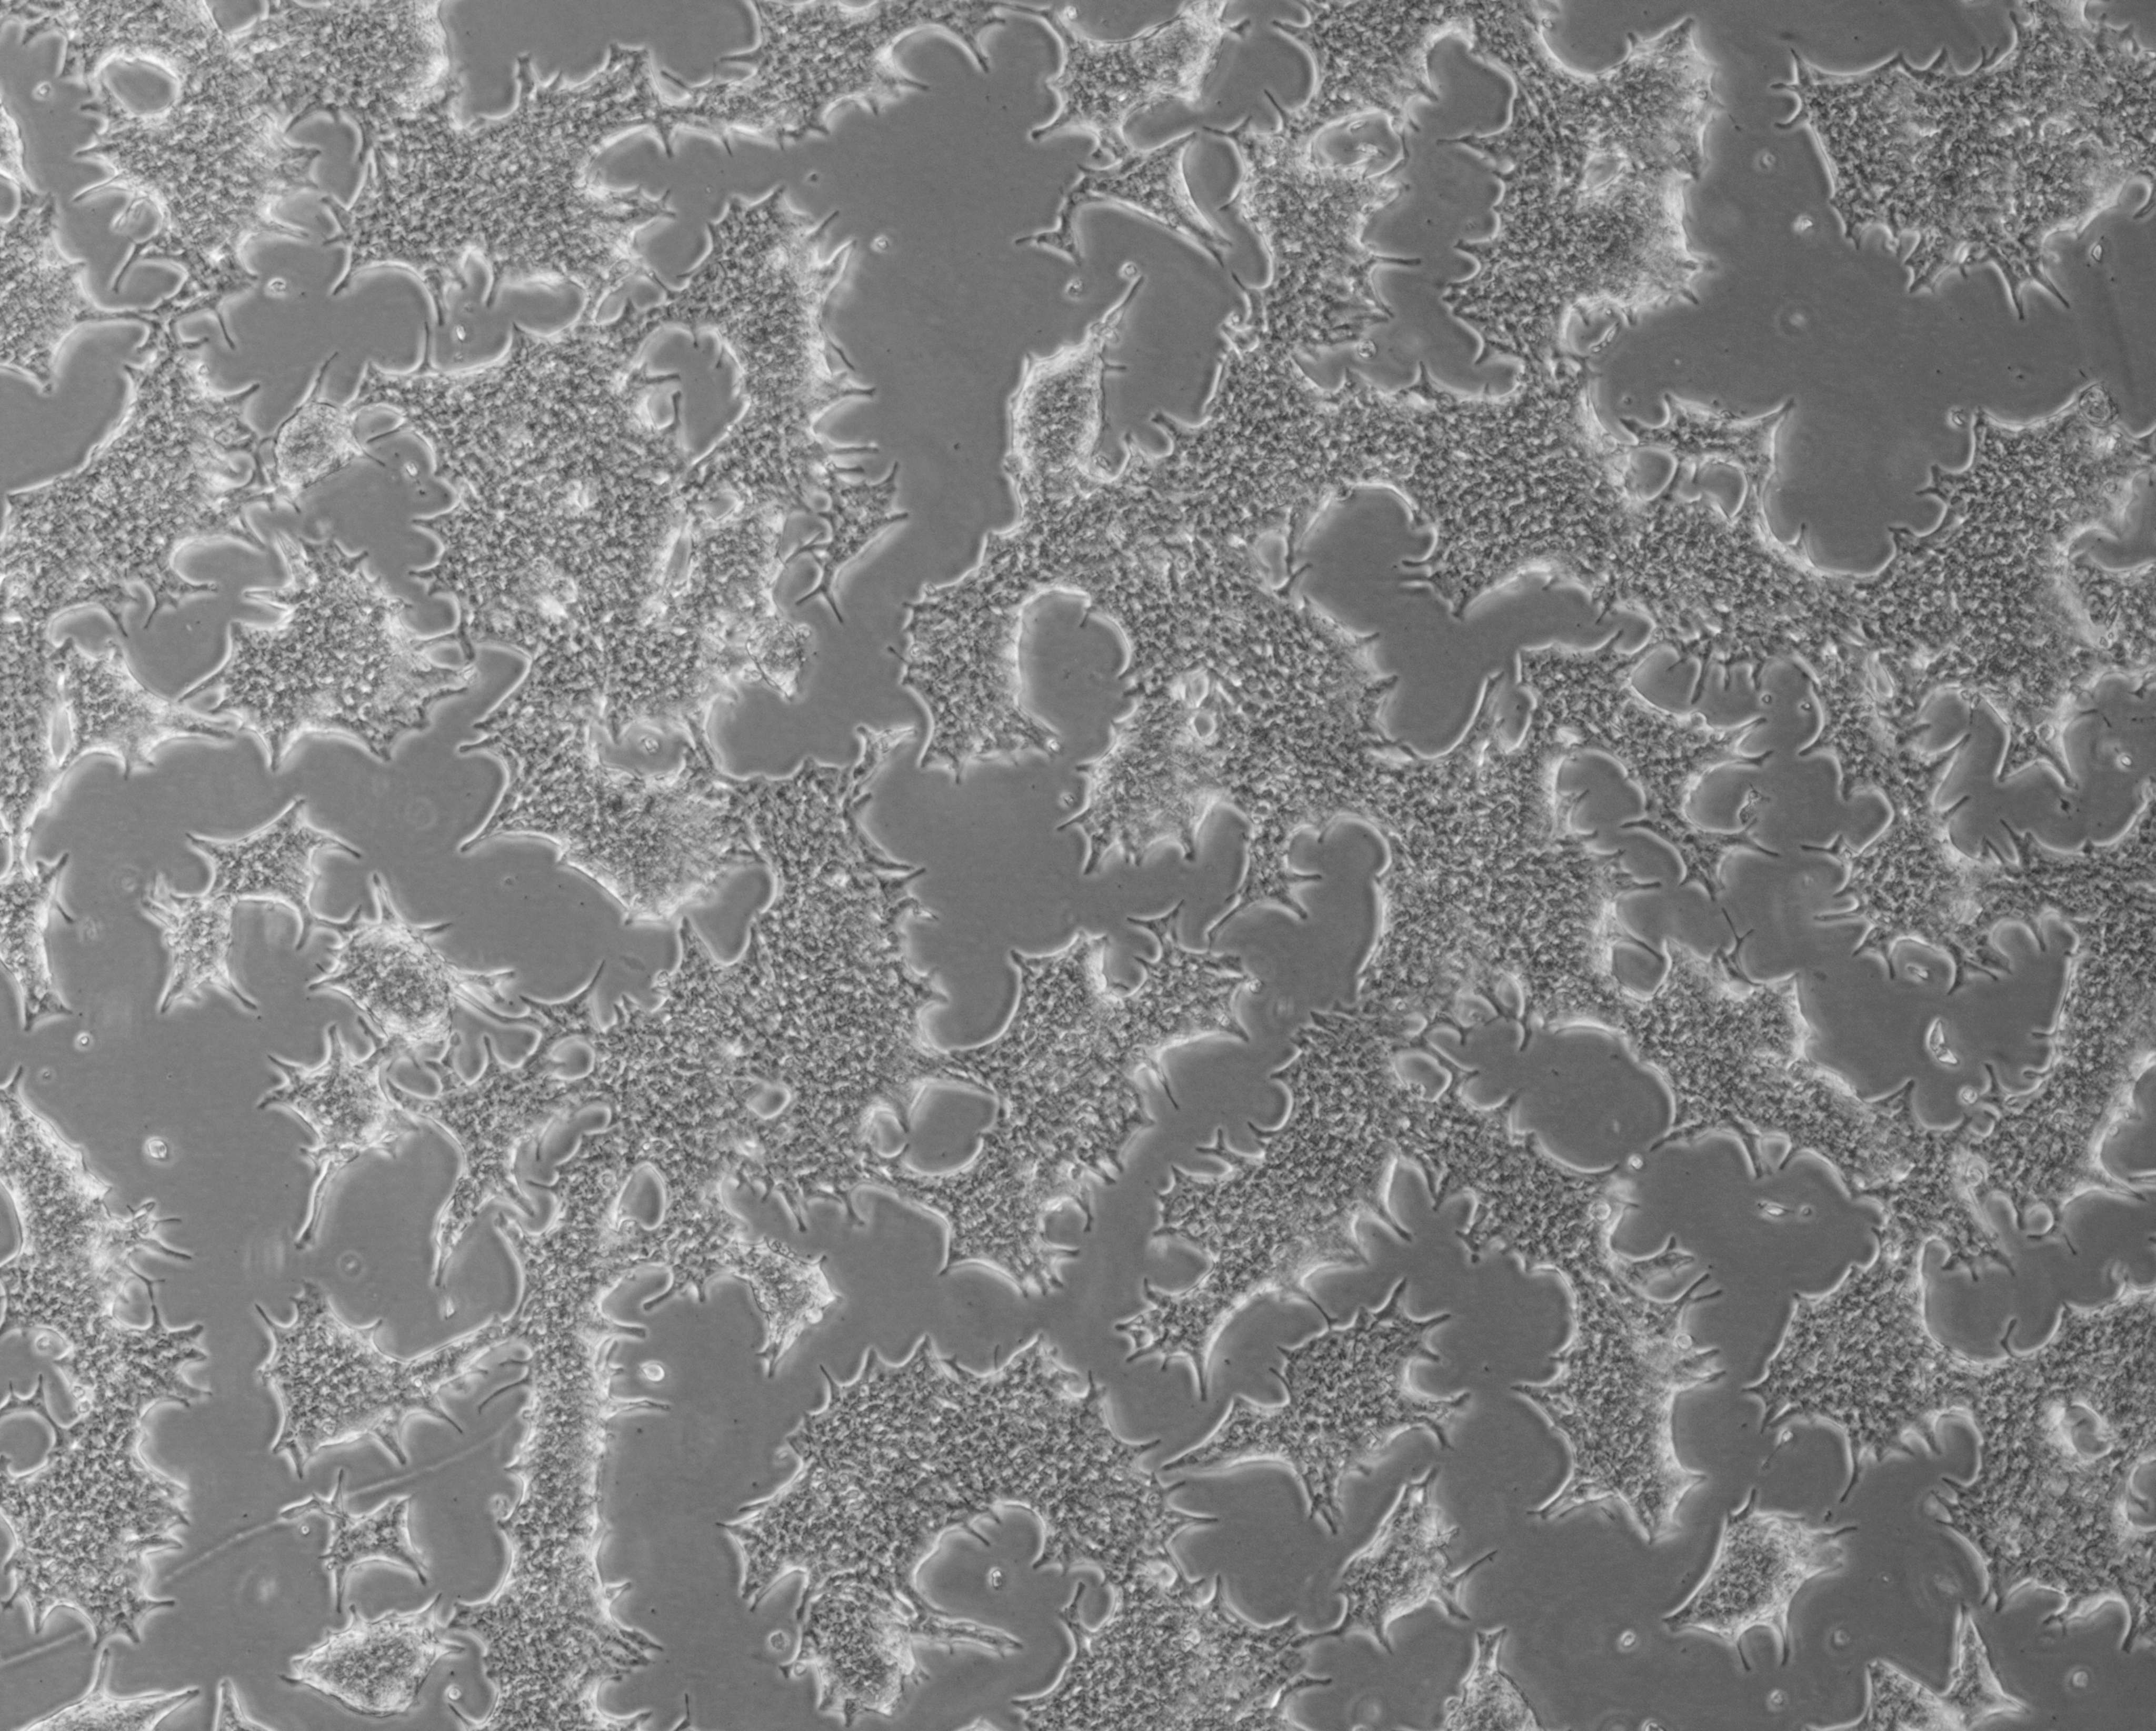

细胞攻略 | SW480(人结肠腺癌细胞)培养教程

细胞简介: SW480 [SW-480]细胞源自50岁Dukes C结直肠癌白人男性患者原位直肠腺癌,后来SW620细胞源自同一病人一年后的淋巴结转移。SW480 [SW-480]细胞表达EGF, CSAp和直肠抗体3阴性,角蛋白阳性。SW480 [SW-480]细胞p53基因第273位密码子的G→A突变引起Arg→His替代,309位密码子的C→T突变导致Pro→Ser替代。SW480 [SW-480]细胞高水平表达p53蛋白,癌基因c-myc、K-ras、H-ras、N-ras、myb、sis和fos的表达呈阳性,癌基因N-myc的表达未做检测,不表达Matrilysin(一种与肿瘤侵袭相关的金属蛋白酶)。有报道称,SW480 [SW-480]细胞表达GM-CSF。SW480 [SW-480]细胞ras原癌基因的12位密码子有一个突变,可以用作PCR法检测该突变的阳性对照。1978年11月,A·Leibovitz将其提交给ATCC时已传代至第91代。SW480 [SW-480]细胞可以用于3D细胞培养和癌症研究,也是一种合适的转染宿主。